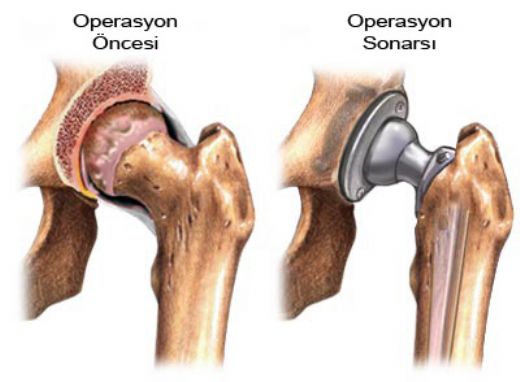

4. Cerrahi Müdahale: Eğer diğer tedavi yöntemleri etkili olmazsa, cerrahi müdahale gerekebilir. Ancak, bu genellikle son çare olarak düşünülmelidir.